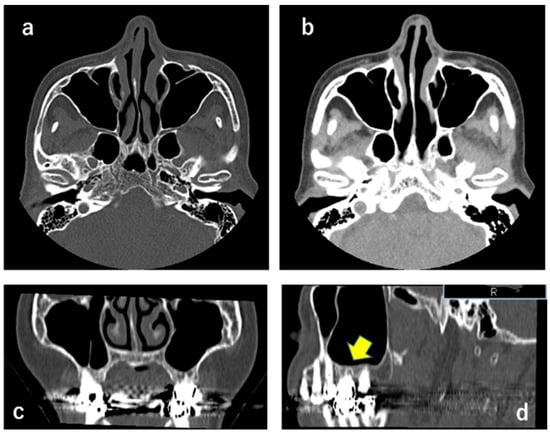

2.1. CT X-ray-Findings